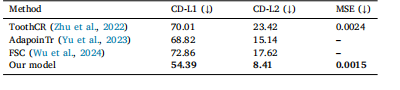

Table 2Comparison of our model with the sate of the art methods in the domain. Metrics arethe same as in Table 1.

表2:我们的模型与该领域最先进方法的比较。所使用的评估指标与表1中的相同。